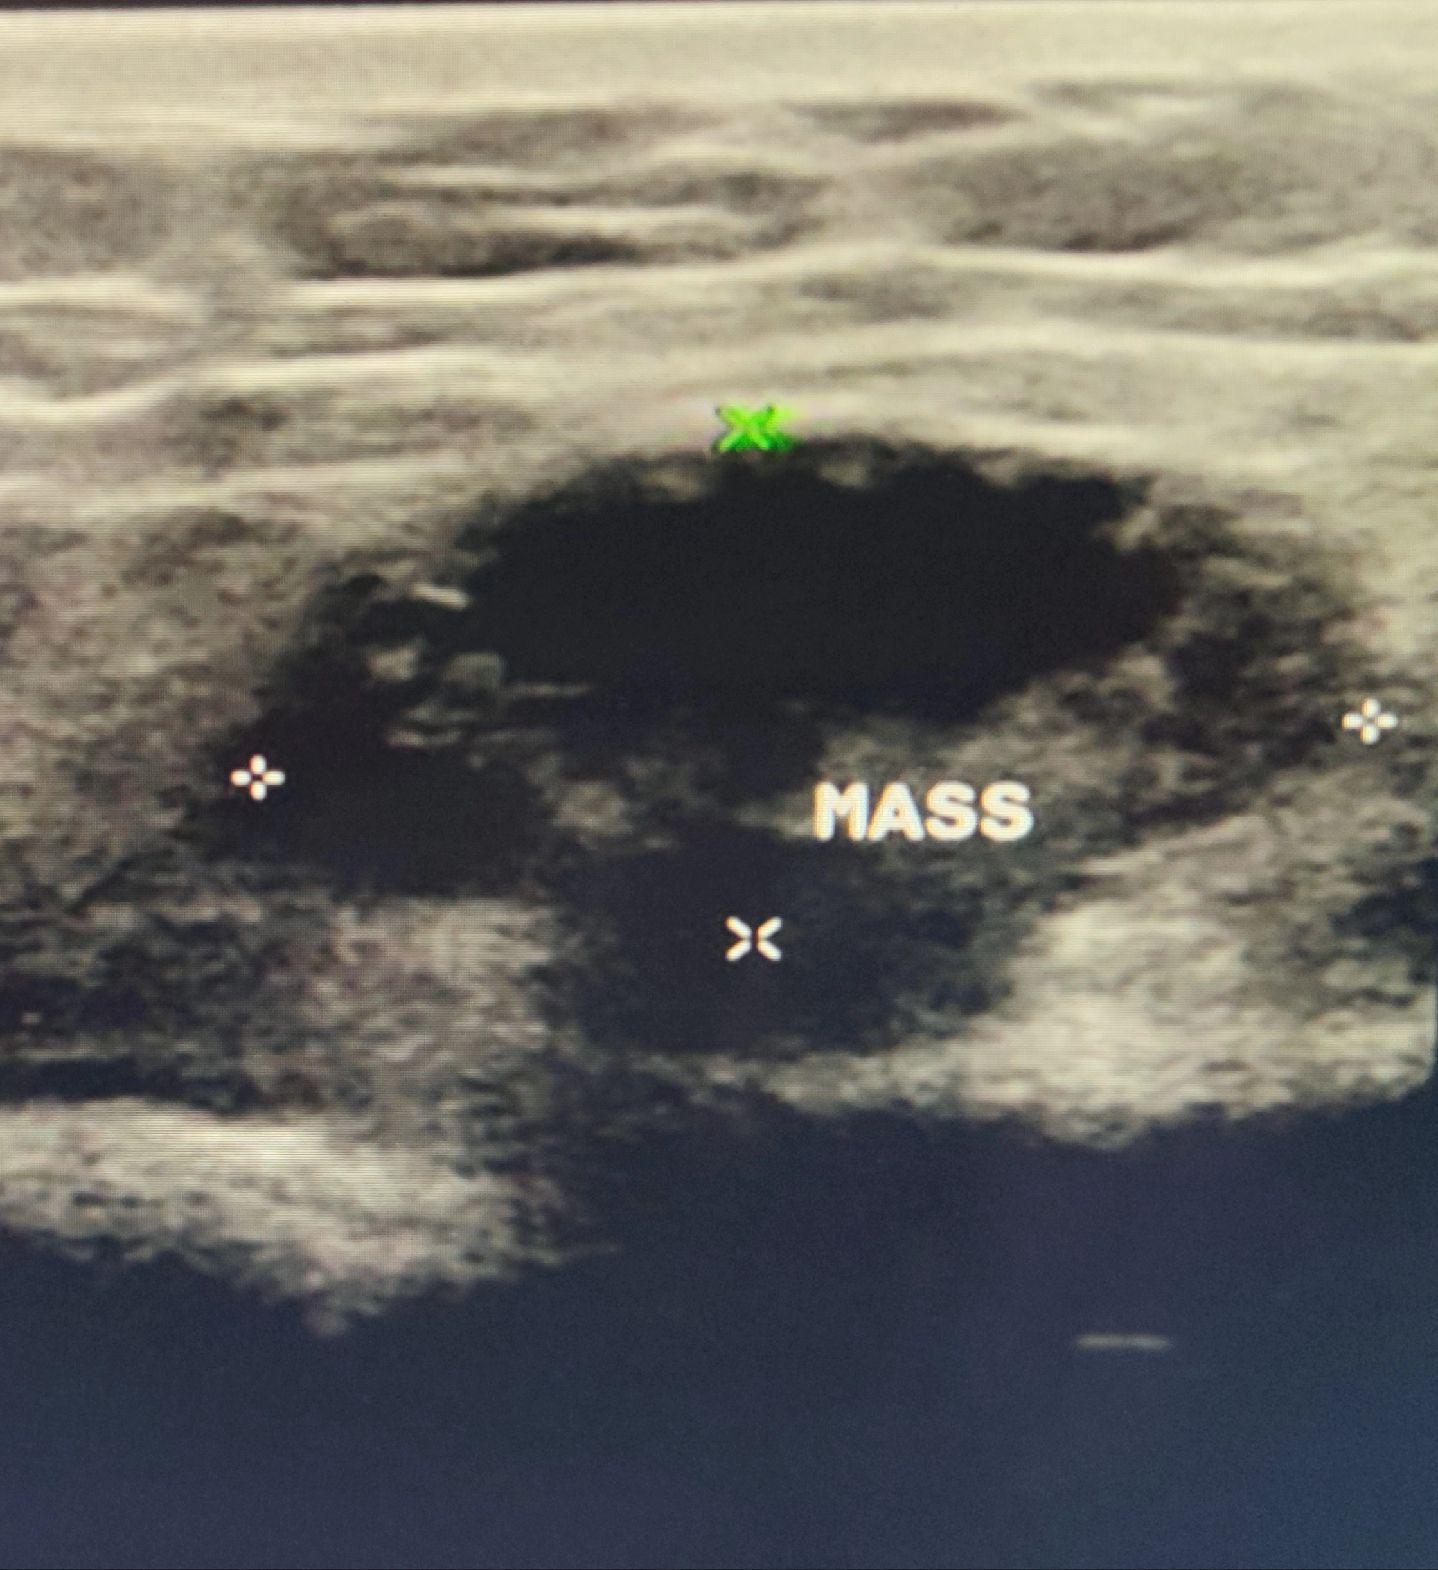

肠疝。只要有缝隙的地方 疝无处不在